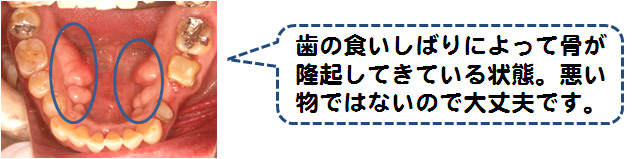

お口の中でも様々な諸症状が診られます!

これらの症状が1つでもあれば口腔外科専門医が居る医院に受診されることをおすすめいたします。又、これらの症状がなくても